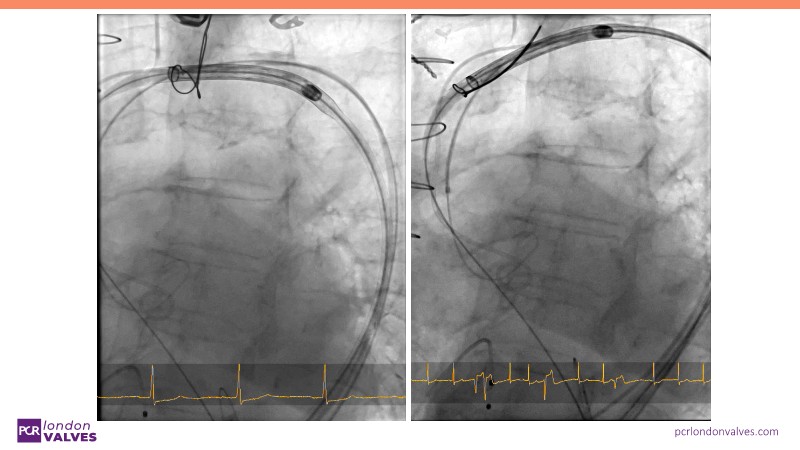

This session offers an in-depth review of complex TAVI cases, focusing on overcoming clinical challenges and achieving optimal outcomes with the Evolut FX+ device. Participants will learn about recent advances in TAVI indications for younger and asymptomatic patients, strategies for managing TAV in surgical aortic valve (SAV) patients including redo TAVI, and explore technological innovations designed to address complex anatomical scenarios.

- To discern the latest technological evolutions that enable the treatment of patients with complex anatomy